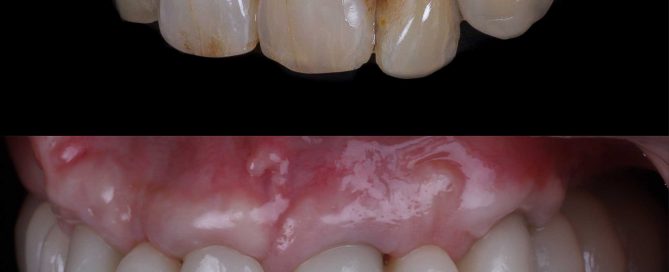

SITUACIÓN INICIAL Paciente que acude a nuestra clínica con signos [...]